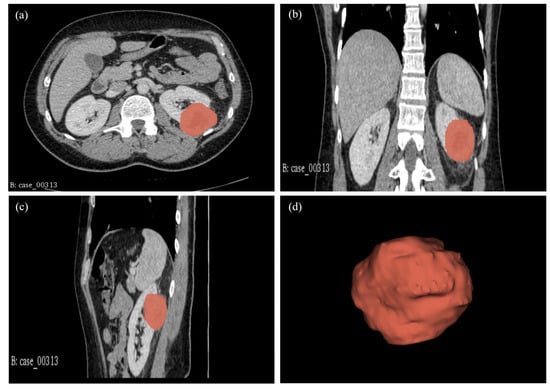

4.5. Tumour Volume Segmentation Technique

4.6. Radiomics Feature Computation